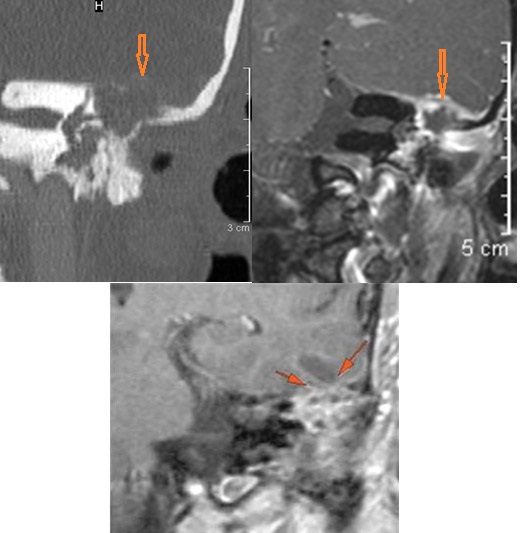

The roof of the mastoid and middle ear are eroded. [Yes/No]

There is dural reactive change,subperiosteal, epidural or subdural abscess long the roof of the mastoid or middle ear or the surfaces of the petrous portion of the temporal bone. [Yes/No]

There is dural reactive change, subperiosteal, epidural or subdural abscess along the roof of the mastoid or middle ear or the surfaces of the petrous portion of the temporal bone. [Yes/No]